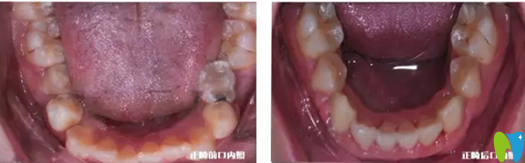

下牙正畸前后對(duì)比照:

小虎牙口腔兒童牙齒正畸下牙正畸前后對(duì)比照